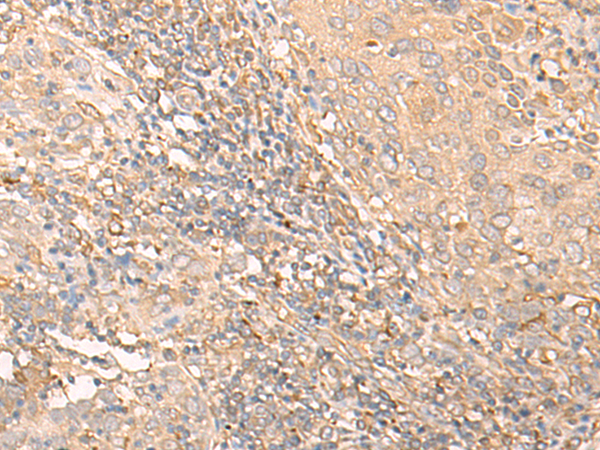

分类: 科研抗体货号: P06466别名: RBM35B应用: WB,IHC反应种属: Human, Mouse, Rat